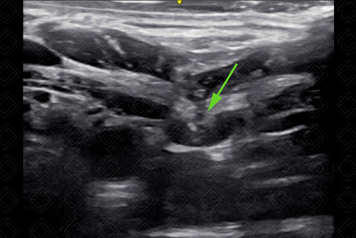

15. Punção guiada por técnica transversal (fora de plano) utilizando-se agulha 18 G (Figuras 5 a 8). [cms-watermark]

Texto alternativo para a imagem Figura 7. Visualização da agulha no momento em que penetra a parede interior da veia (seta verde). Créditos: Dr. Igor Biscotto - Rio de Janeiro/RJ.